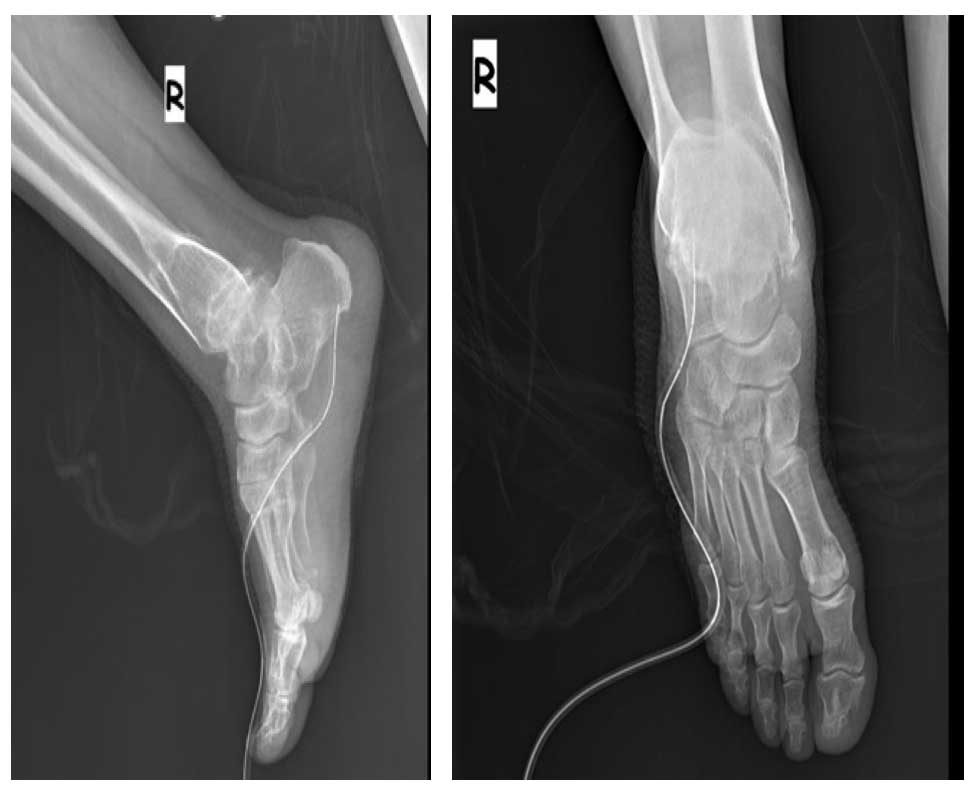

Ameliyat Öncesi: Çoklu osteokondrom ve kalkaneus yerleşimli kondrosarkom görülmekte.